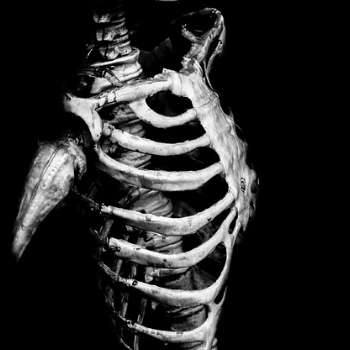

골다공증은 뼈의 밀도가 낮아지고 뼈 조직의 미세구조가 변형되어 뼈가 약해지는 질환입니다. 이로 인해 골절 위험이 증가하며, 특히 노인들에게 흔하게 발생합니다. 골다공증은 초기에는 특별한 증상이 없지만, 시간이 지남에 따라 다양한 증상이 나타날 수 있습니다. 여기에서는 골다공증의 주요 증상 10가지를 전문가적 관점에서 상세히 설명하겠습니다.

골다공증의 가장 중요한 특징 중 하나는 뼈의 취약성이 크게 증가한다는 점입니다. 뼈가 약해져서 작은 충격이나 일상적인 활동에서도 쉽게 골절이 발생할 수 있습니다. 특히 척추, 고관절, 손목 등의 부위에서 골절이 자주 발생하며, 이러한 골절은 심각한 통증과 기능 장애를 초래할 수 있습니다. 예를 들어, 갑작스러운 낙상이나 가벼운 부딪힘으로 인해 손목 골절이나 고관절 골절이 발생할 수 있으며, 이는 환자의 일상생활에 큰 영향을 미칩니다.